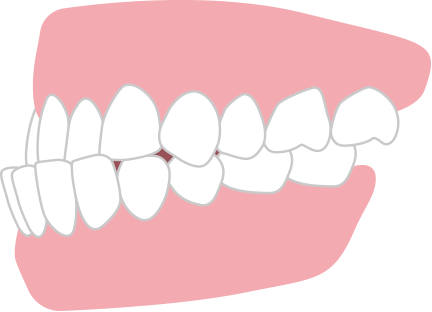

出っ歯 上顎前突

上の歯が前方に突出している状態。

唇が閉じにくく、口呼吸・ポカン口の原因になります。また上唇が前方に突出したお顔つきになります。重度の出っ歯の場合は矯正歯科治療が保険適用になります。